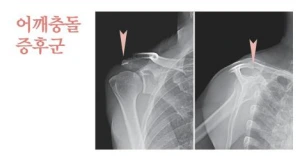

어깨충돌증후군(Impingement Syndrome)이란?

어깨의 힘줄인 회전근개가 그 위에 위치한 견봉의 뼈와 부딪히면서 염증을 일으키는 질환을 말합니다. 쉽게 말하면 어깨 내에 존재하는 조직들에 마찰이 발생하면서 생기는 통증을 말합니다. 염증이 생기게 되면 통증이 발생하게 되어 운동을 하기 어렵고 일상생활에서도 불편함을 초래하는 질환입니다.

어깨충돌증후군이 의심되는 환자분들의 경우는 먼저 엑스레이 촬영을 통해서 진단을 시작합니다. 어깨를 덮고 있는 뼈의 모양이 굽어져 있는지, 어느 정도 진행이 되었는지 확인한 이후에 치료를 다르게 적용하는데요. 초기 단계에 발견하는 경우에는 점액낭의 염증 반응을 가라 앉혀 주는 것만으로도 충분하므로 약물이나 재활 치료 등의 간단한 방법을 통해 증상이 나아진답니다.